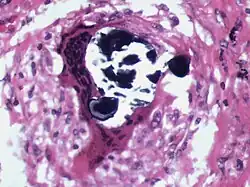

Schaumann differenzierte die verschiedenen Syndrome der von Ernest Besnier als Lupus pernio und von Cæsar Peter Møller Boeck als benignes Sarkoid bezeichneten Sarkoidose (Morbus Besnier-Boeck-Schaumann) und definierte dieses Krankheitsbild als Allgemeinkrankheit, die auch innere Organe befällt.[2] Seine entsprechende Arbeit mit dem Titel Sur le lupus pernio, die er im November 1914 vorlegte, wurde von der Societé Francaise de Dermatologie ausgezeichnet.[3] Die bei Sarkoidose auftretenden Schaumann-Körper oder Schaumann-Körperchen sind nach ihm benannt. Hierbei handelt es sich um kleine Einschlüsse innerhalb von Langhans-Riesenzellen.[4] Aufgrund seines Beitrags zur Erforschung der Sarkoidose wird diese Erkrankung auch als Morbus Besnier-Boeck-Schaumann bezeichnet.[5]